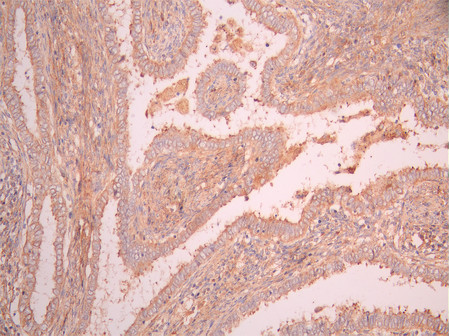

IHC image of CSB-RA964035A0HU diluted at 1:100 and staining in paraffin-embedded human endometrial cancer performed on a Leica BondTM system. After dewaxing and hydration, antigen retrieval was mediated by high pressure in a citrate buffer (pH 6.0). Section was blocked with 10% normal goat serum 30min at RT. Then primary antibody (1% BSA) was incubated at 4°C overnight. The primary is detected by a Goat anti-rabbit polymer IgG labeled by HRP and visualized using 0.05% DAB.